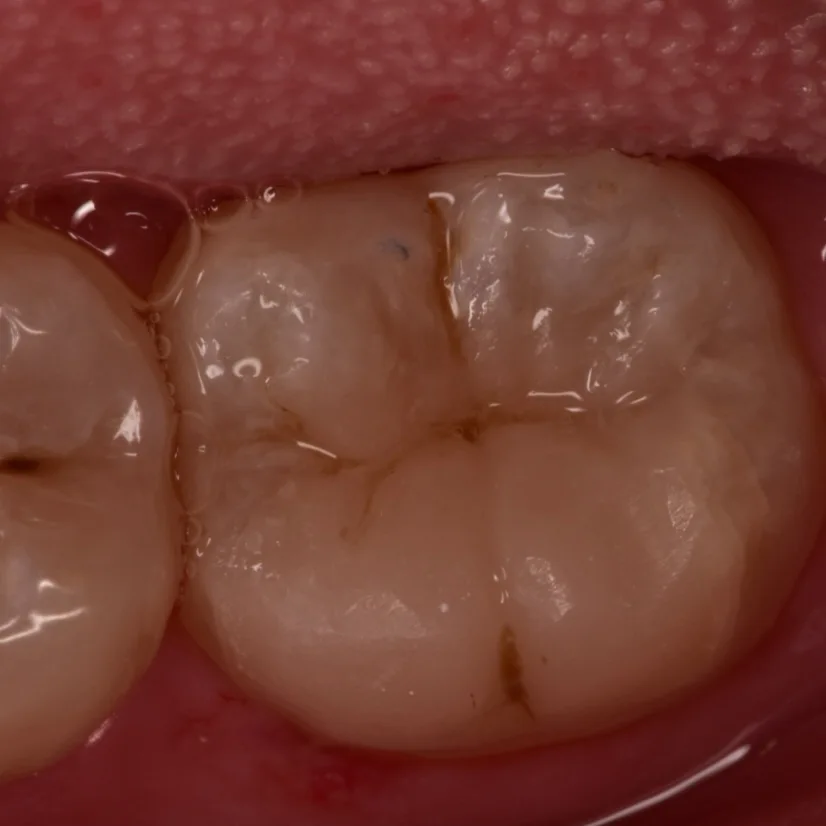

Simple Finishing and polishing

Final result

Try to mimic the nature as could as possible